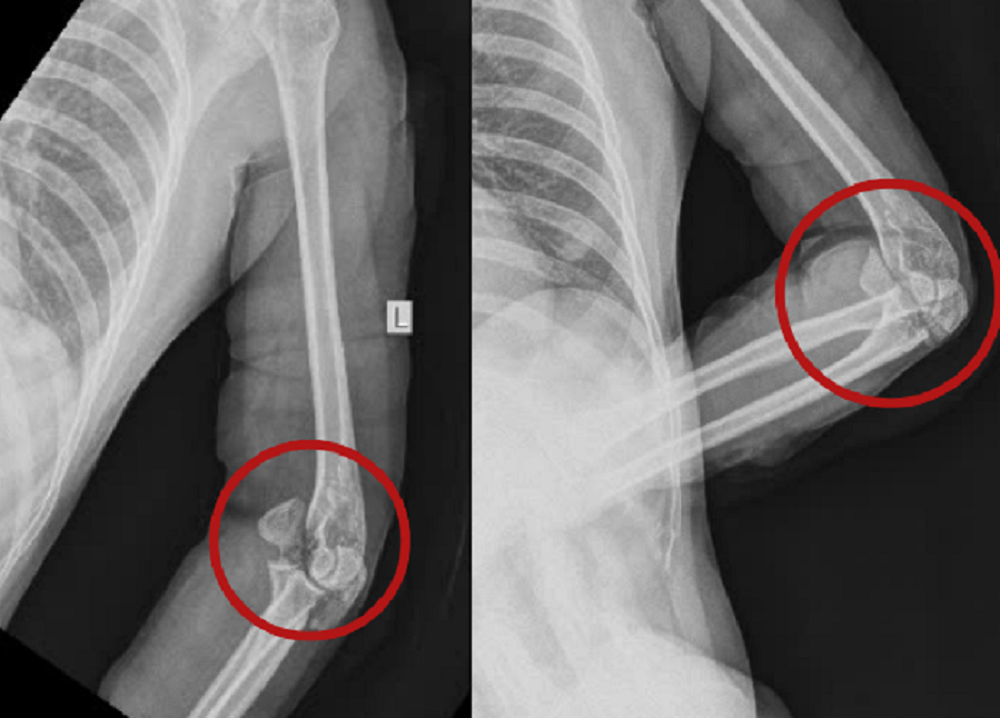

| Những nhát chém chí mạng khiến nạn nhân bị vỡ xương khuỷu tay (khu vực khoanh tròn) |

Theo BS Quang Nhật, khi tiếp nhận, qua thăm khám, chẩn đoán hình ảnh, các bác sĩ ghi nhận, vùng vai, cánh tay, cẳng tay, bàn tay cả hai bên của nạn nhân có nhiều vết thương dài và sâu, lộ gân, đứt cơ. Vùng khuỷu trái bị vết chém chí mạng gây gãy xương mỏm khuỷu, gãy xương lồi cầu trong xương cánh tay, lộ khớp khuỷu trái.